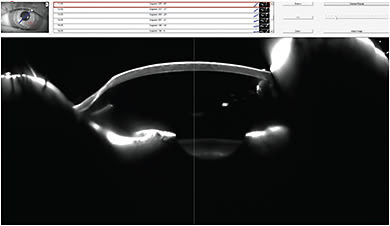

Lens Fitting and Follow-up Care The patient’s left eye was diagnostically fit with a 16mm Europa (Visionary Optics) scleral contact lens with parameters of 52.00D base curve radius (BCR) and –6.00D power. The patient’s vision OS at the dispensing visit was 20/25. The scleral lens had complete central corneal clearance and fit without excessive compression (Figures 2, 3, and 4). (Click here to view a video of an optic section assessment showing acceptable clearance of a scleral lens courtesy of Dr. DeNaeyer.)

Figure 4. An optic section reveals good apical clearance for the left scleral lens in Case #1.